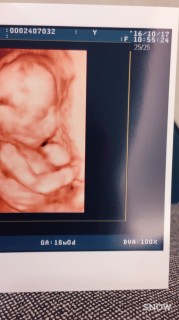

BPD(頭の幅) 45.3ミリ AC(腹部周囲長) 129.2ミリ FL(大腿骨長) 25.1ミリ 体重は225グラム、頭からお尻まで13センチで足を伸ばせば20センチ弱とのこと。 順調だそうです♪ 『ぜひとも性別をお願いします!』で、エコー開始数秒で写真の通り男の子と判明(笑)。 お母ちゃんの気持ちが伝わったかな? 地味に動いていてかわいかった~♪ 胎動はこれかな?というのはあるのですが、確信が持てず…。 先生は全然問題ないですよーとおっしゃっていました! 次回4週間後も楽しみです(^∀^)